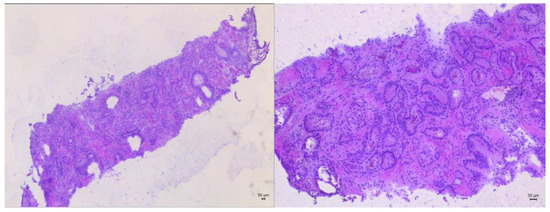

Metastatic Carcinomas at the Episiotomy Site: A Systematic Literature Review

Background/Objectives: Rarely, primary (PriCs) or metastatic (metECs) carcinomas occur in the episiotomy site. Methods: A systematic literature review of metECs was carried out. We reviewed the PRISMA guidelines and the Scopus, Pubmed, and Web of Science databases. Results: We found 21 carcinomas; all of them were cervical carcinomas (11 squamous, SCC; 6 adenocarcinomas; 3 adenosquamous; 1 SCC or adenocarcinoma) diagnosed during pregnancy (38%) or 0.25–8 months postpartum (57%). SCCs were larger (mean size: 4.8 cm). At presentation, only two cases were pN+, and no distant metastases were found, excluding four episiotomy metastases (one anticipating the cervical cancer diagnosis); the remaining episiotomy metastases (mean size: 3 cm; one multifocal) were found at follow-up (these were first metastases in 86% of cases). The time range from the episiotomy/last delivery to first episiotomy metastasis was 1–66 (mean, 12.3) months. Treatment was variable: hysterectomy (71%) ± lymphadenectomy (67%) and/or adjuvant treatment (19%); chemoradiation/radiotherapy alone (24%). A total of 90% of cases recurred after 18 days to 66 months (mean, 12 months). At last follow-up, ten patients (48%) were disease-free after 12–120 (mean, 63.5) months, two patients (10%) were alive with disease, and nine (42%) patients died of disease after 6–36 (mean, 12.5) months (including two never-cleared/progressing cases). Conclusions: PriCs and metECs are rare. Iatrogenic/obstetric implantation or vascular dissemination of cervical cancer at the site of episiotomy may occur. For episiotomy lesions, accurate gynecological/perineal examination is required, and biopsy can be considered. Larger studies are required in order to determine treatment guidelines. Compared to PriCs, metECs occurred in younger (premenopausal) patients, were not associated with endometriosis, and demonstrated slightly smaller size and shorter mean time from episiotomy to episiotomy metastases, with a higher likelihood of a less favorable prognosis. Full article

Figure 1